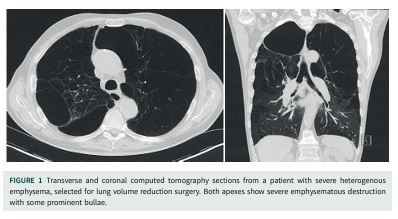

Volume reduction is a disease-modifying treatment that aims to reshape the diseased lung towards a more normal total lung capacity by removing severely damaged and overinflated lung parenchyma. It is an effective therapeutic strategy in well-selected patients, resulting in improvements in exercise tolerance, lung function, quality of life and survival. The most widespread strategies for volume reduction are either video-assisted thoracoscopic surgery or bronchoscopic lung volume reduction. It is crucial to decide which approach would be more suitable for specific patients, as this is related to the outcome of the procedure. Factors like emphysema distribution on computed tomography, the presence or absence of collateral ventilation, the patient’s pulmonary function tests, a history of other comorbidities and previous interventions might all influence the choice of procedure. It is crucial that this decision is taken by a multidisciplinary expert team to have the best outcome and fewer complications.